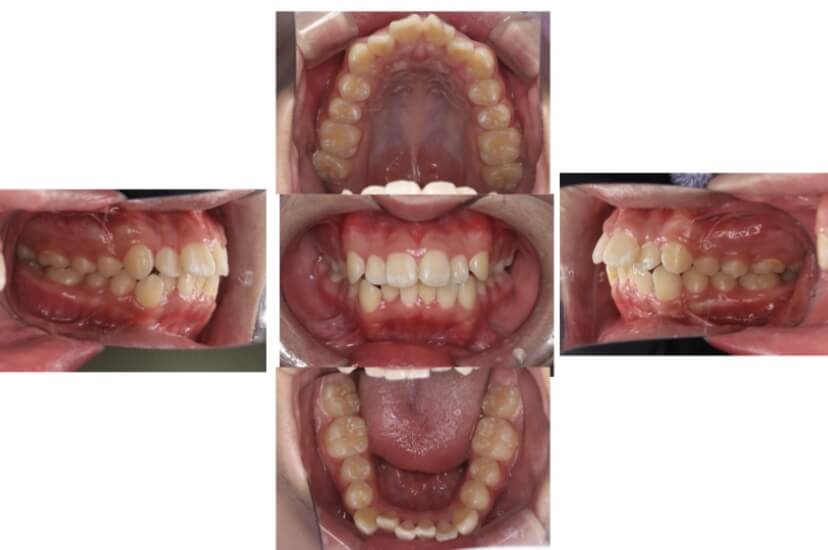

BEFORE

AFTER

症例3

叢生

抜歯

ブラケット矯正

上下顎叢生(上下の前歯のガタガタ)のケースです。

装置はラビアル(上下表側)で、上下顎の小臼歯を4本抜歯を行っています。抜歯したスペースを使って、上下の前歯の後方移動と叢生(ガタガタ)の改善を行っています。

主訴 八重歯を治したい。

年齢・性別 25歳 女性

お住まいの地域 神奈川県川崎市

治療方針 抜歯スペースを利用して上前歯の叢生(ガタガタ)の改善

抜歯部位 上下顎左右第一小臼歯

使用装置 ラビアル(上下表側)、顎間ゴム

治療期間 1年11か月

治療回数 16回

リテーナー クリアリテーナー